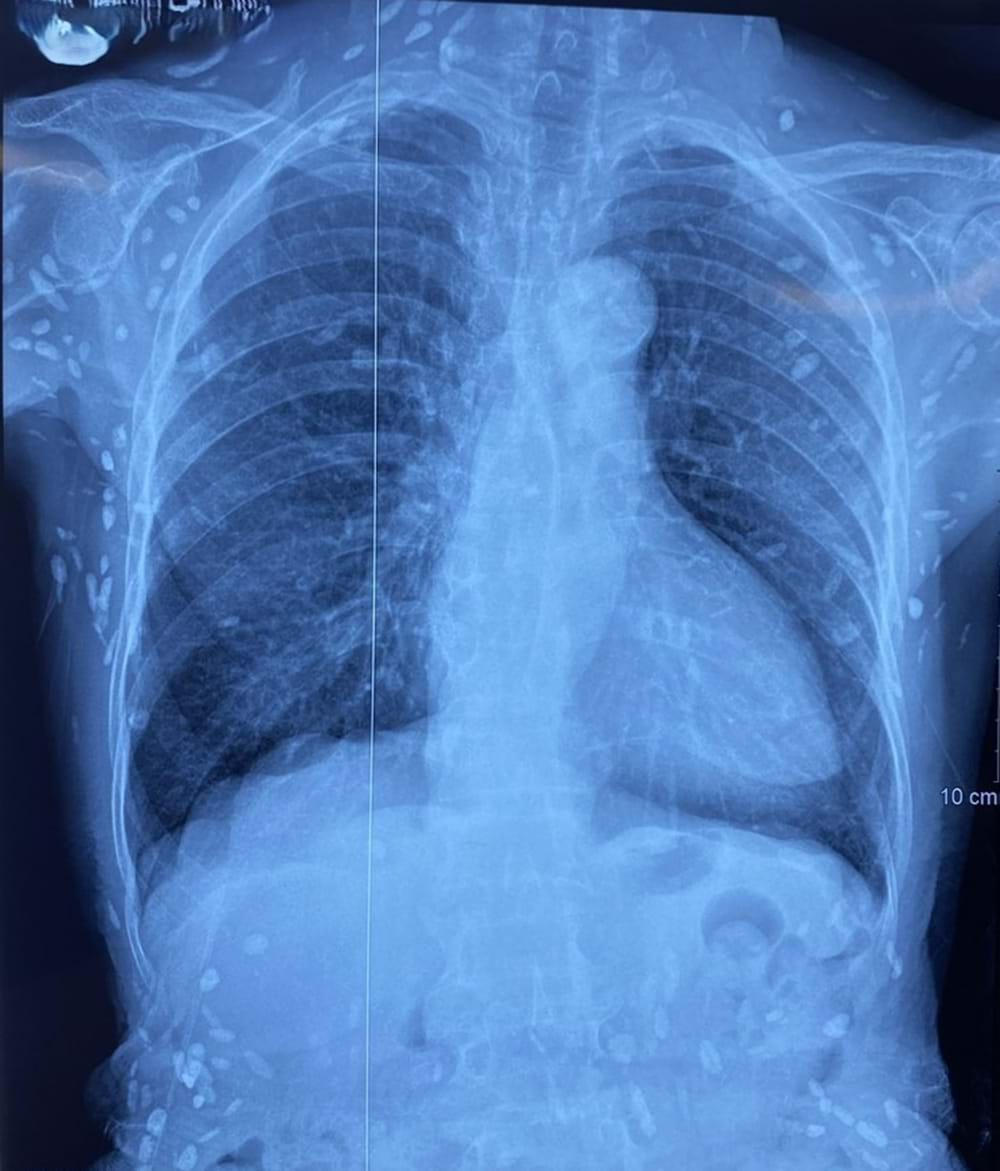

Gần đây khoa Hồi sức truyền nhiễm - Viện Lâm sàng các bệnh Truyền nhiễm (Bệnh viện Trung ương Quân đội 108) tiếp nhận một người bệnh nữ sinh năm 1948 được chẩn đoán theo dõi nhiễm ấu trùng sán dây lợn. Người bệnh được chuyển lên từ tuyến trước vì rối loạn ý thức đe dọa suy hô hấp, hình ảnh cắt lớp vi tính sọ não và X-quang ngực cho thấy rất nhiều nốt cản quang trong nhu mô não và dưới da vùng ngực-bụng.

Nhiều nốt cản quang dưới da thành ngực - bụng và chi trên

Một vài u cục với kích thước tương ứng có thể sờ thấy dưới da vùng ngực và cánh tay của người bệnh. Mặc dù xét nghiệm kháng thể IgM với sán dây lợn âm tính, các tổn thương trên X-quang gợi ý người bệnh trước đây bị nhiễm ấu trùng sán dây lợn, sau đó các nang sán trở nên vôi hóa và tồn tại lâu dài trong tổ chức.

Người bị nhiễm sán lợn do ăn phải nang sán trong thịt lợn gạo không nấu chín hoặc trứng sán có trong rau sống. Ở người, ngoài vị trí cơ, nang sán có thể được hình thành tại các vị trí nguy hiểm như não, mắt, và có thể gây ra các triệu chứng tại cơ quan này như động kinh, rối loạn tâm thần - vận động, đau đầu, đau mắt, giảm thị lực, … Nang sán dây lợn có thể tự thoái hóa hoặc bị vôi hóa, tạo nên nhiều hình ảnh cản quang phát hiện được trên phim X-quang như trường hợp bệnh nhân trên.